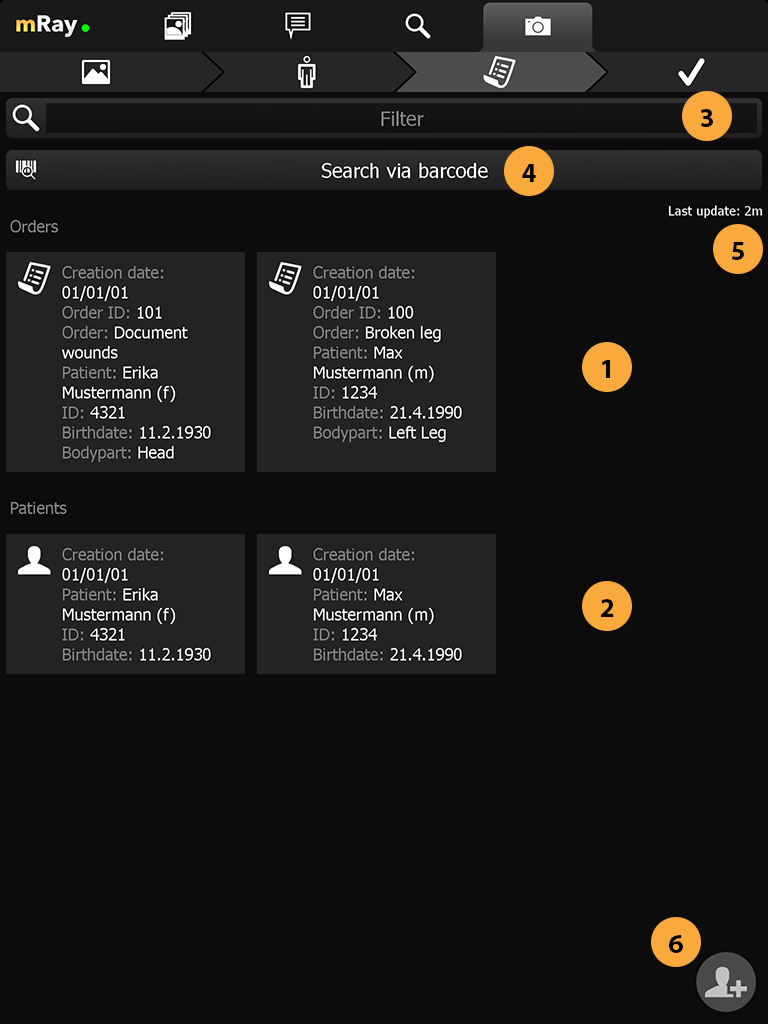

15.4. Orderview

In this page all patients and unprocessed orders are displayed. Each order/patient are displayed with the necessary information to identify them (Point 1). To filter all the entries you can use the search field in the top (Point 3). To scan a QR or Barcode you can use the corresponding button below the search field (Point 4).

-

Shows patients that are registered in the system.

-

Shows orders that are registered in the system.

-

Filter input to filter the displayed results.

-

Search patient or order by scanning a bar code containing the patient or order id.

-

Shows when the last update or order id has been made.

-

Add a patient to the system by manually entering the correct information.

By clicking an order/patient you’ll proceed to the confirm. If there is no order and no patient that fits your case you’ll want to add the patient manually with the add patient button (Number).